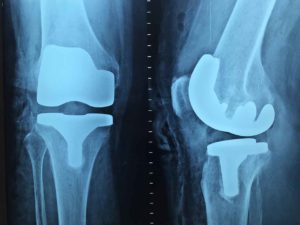

Um eines klarzustellen: Heilung gibt es bei Arthrose nicht! Was zerstört ist, kann nicht wieder aufgebaut werden. Klinische Studien zeigen vielversprechend, dass Weihrauchkapseln die Schmerzsymptomatik und damit die Bewegungseinschränkungen bei altersbedingter Arthrose vermindern können. Ist die Abnutzung jedoch zu weit fortgeschritten, hilft nur noch eine Operation, bei der das betroffene Gelenk durch ein künstliches ersetzt wird.